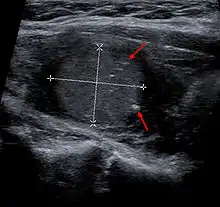

بالنسبة للمرضى الذين يعانون من شكل متقطع (غير وراثي) من سرطان الغدة الدرقية النخاعي، قد يتشكل نتوء أو "عقيدة" داخل الغدة الدرقية غالبًا ما تخرج من جانب الغدة الدرقية أو أمامها. لذلك، يتم تشخيص معظم سرطانات الغدة الدرقية النخاعية، مثل جميع سرطانات الغدة الدرقية الأخرى، بعد أن يشعر الطبيب برقبة المريض أو الموجات فوق الصوتية أو غيرها من الأشعة السينية تلاحظ وجود كتلة داخل الغدة الدرقية.

عند اكتشاف عقيدة الغدة الدرقية، يجب إجراء فحص جسمي كامل. عند احراء الفحص، يبحث الطبيب عن عوامل خطر الإصابة بالسرطان والتي تشمل: تاريخ عائلي للإصابة بسرطان الغدة الدرقية، وتاريخ التعرض الإشعاعي للرأس والرقبة و/أو الصدر، وعمر أقل من 20 عامًا، وعمر أكبر من 70 عامًا، وجنس المصاب والعقيدات الصلبة جدًا والعقد الليمفاوية المتضخمة و/أو بحة في الصوت. بعد ذلك، يجب فحص مستوى TSH لمعرفة ما إذا كان لدى المريض سوي الدرقية (أي وظيفة الغدة الدرقية العادية) أو فرط نشاط الغدة الدرقية أو قصور الغدة الدرقية. بشكل عام، من غير المعتاد أن يصاب مرضى فرط نشاط الغدة الدرقية بالسرطان بينما قد يكون لدى مرضى قصور الغدة الدرقية معدل إصابة بسرطان الدرقية بنسبة أعلى قليلاً. معظم مرضى سرطان الغدة الدرقية هم في حالة سوي الدرقية. في حالة الاشتباه بالإصابة بسرطان الغدة الدرقية النخاعي، يجب فحص مستويات الكالسيتونين و CEA. من المرجح أن تكون مستويات الكالسيتونين أعلى من المعتاد في المرضى الذين يعانون من سرطان الغدة الدرقية النخاعي ويمكن استخدامها كمقياس تقريبي لكمية المرض الموجودة في الجسم. بشكل عام، كلما زاد الكالسيتونين، كلما زاد المرض. قد تكون المستويات العالية من CEA (أي المستضد السرطاني المضغي) علامة على شكل أكثر عدوانية من سرطان الغدة الدرقية النخاعي.

يتم إجراء التشخيص في المقام الأول عن طريق الخزعة بالإبرة الدقيقة لآفة الغدة الدرقية لتمييزها عن أنواع أخرى من آفات الغدة الدرقية.[9] سيظهر الفحص المجهري سدى نشواني مع تضخم في الخلايا المجاورة للجريب.